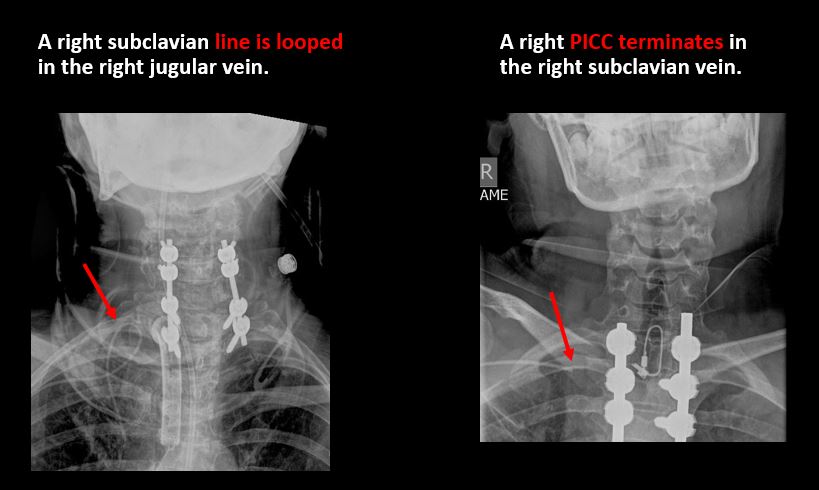

There is air or a foreign body or other abnormality in the soft tissues of the lower head, neck or upper thorax.

There are post surgical changes of the bones or soft tissues of the lower head, neck, or upper thorax.